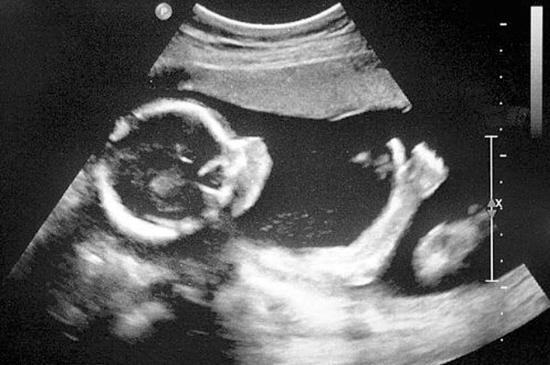

6.孕10周:这时候可以看见宝宝颈背部的皮肤级皮下组织啦,还可以数出宝宝的手指,肢体活动相当活跃。